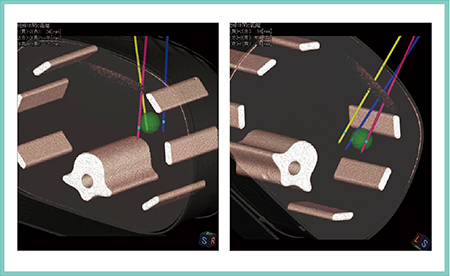

3D Sim-Navigator では,RVSにて同期表示された超音波画像とほぼ同一断面のCTやMRIのMPR画像上で腫瘍にマーキングを行うと,超音波画像上でも腫瘍がマーキングされる。そこに超音波ガイド下に電極針を穿刺し,針のマーキングを行う。この電極針を履歴登録して三次元ボリュームデータに反映させると穿刺ガイドラインが表示され,3D画像の中で腫瘍と電極針のオリエンテーションをつけることが可能となる。複数本穿刺では腫瘍と各電極針との位置関係が非常に明瞭となるため(図1),マルチポーラRFAやオーバーラップ法においては,きわめて有用なシミュレータとなる。

図1 シミュレータとしての3D Sim-Navigator